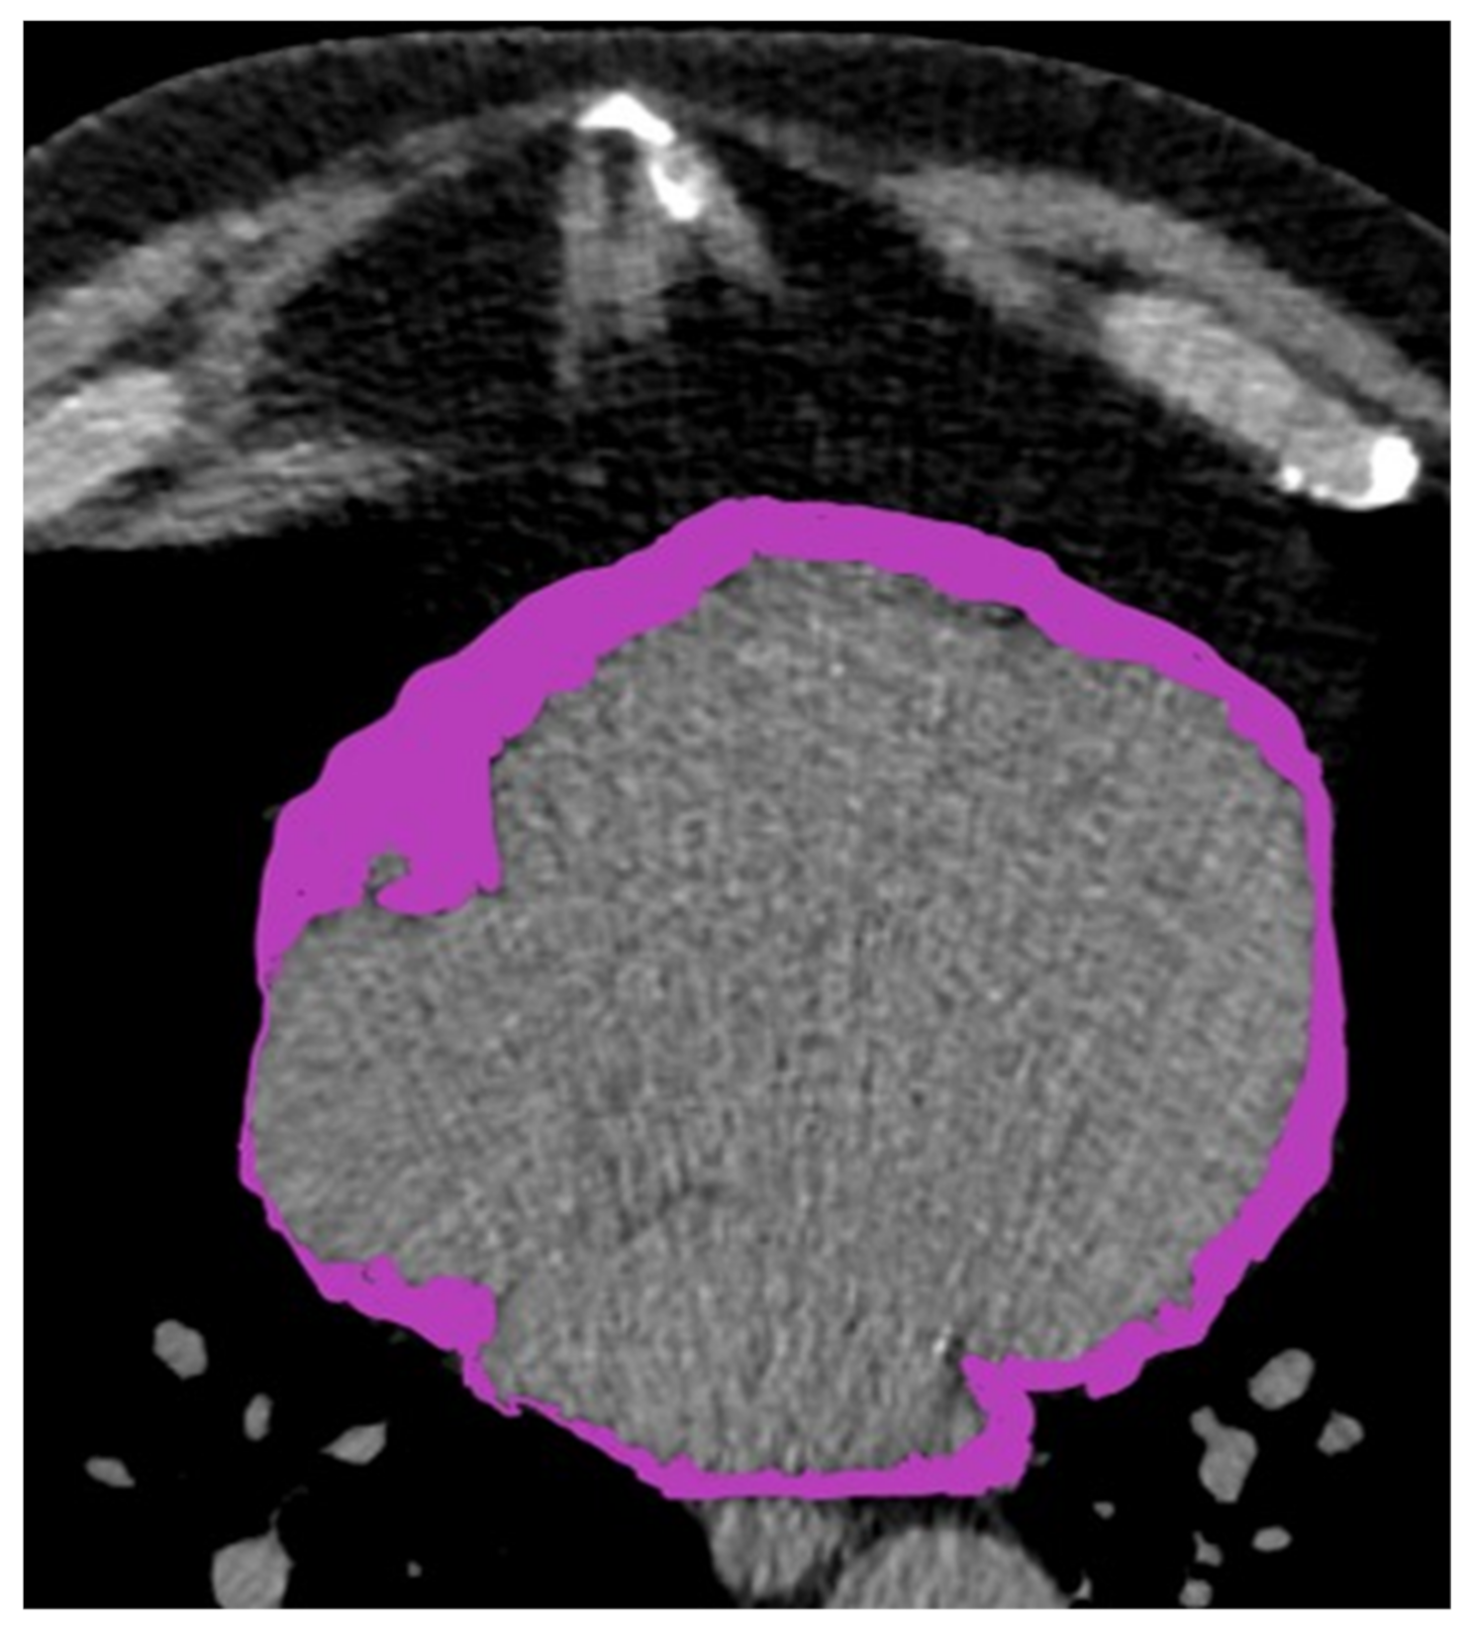

2.3. Pericardial Fat Assessment Protocol